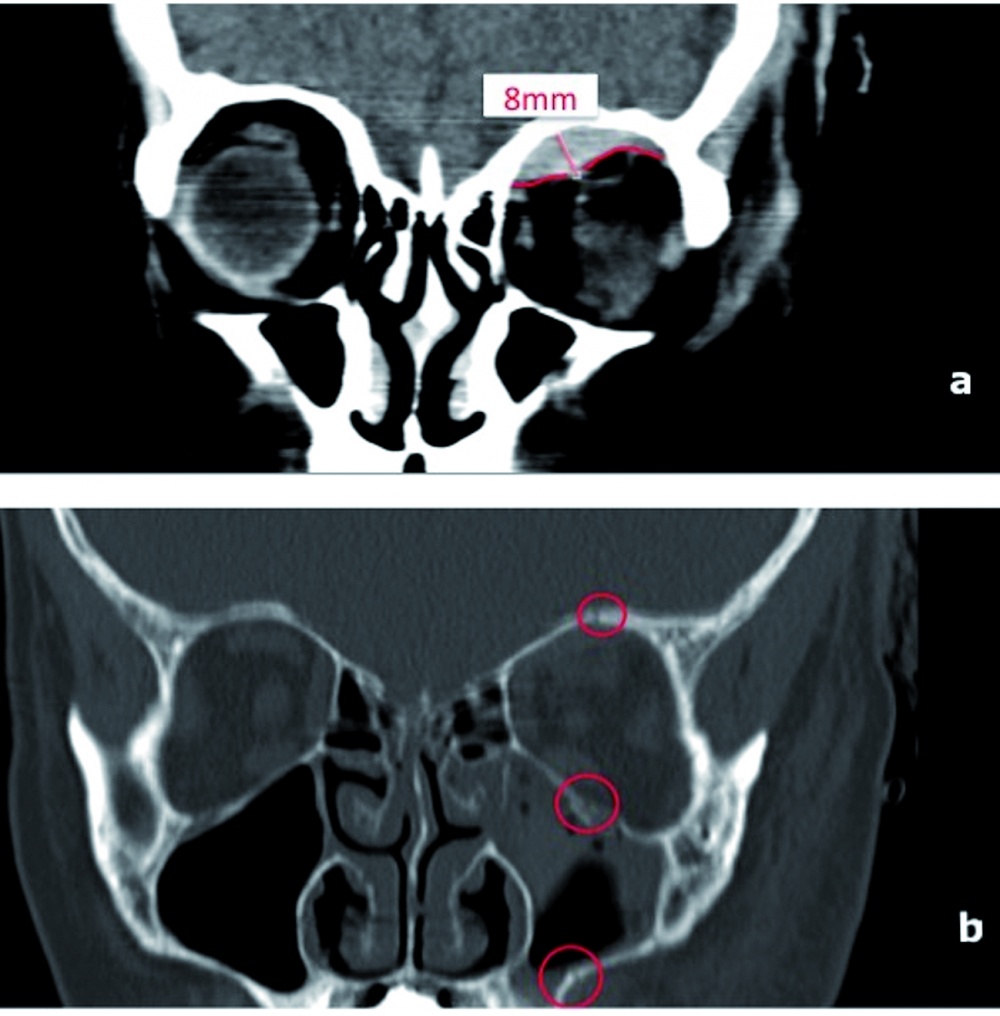

Neuro- und Viscerokraniums sind im Weichteil- (a) und Knochenfenster

(b) abgebildet. In Abb. 1a ist das Ausmaß des intraorbitalen

Hämatoms (rote Markierung) nachvollziehbar. Der maximale

koronare Durchmesser des Hämatoms lag bei 8 mm. Abb. 1b zeigt die

Frakturen von Orbitadach und -boden sowie Seitenwand des Sinus

maxillaris links (rote Kreise). Darüberhinaus erkennt man den

Hämatosinus maxillaris links. (Bild: BwKrhs Westerstede, FU-Stelle

8 – Radiologie)

In der CT-Untersuchung des Neuro- und Viscerocraniums sowie der Halswirbelsäule konnte eine gering dislozierte Mittelgesichtsfraktur mit Beteiligung der lateralen Wand des Sinus maxillaris links, des Orbitadachs und Orbitabodens links nachgewiesen werden (Abbildung 1b). Es imponierte darüberhinaus ein intraorbitales, raumforderndes, vermutlich subperiostales Hämatom entlang des Orbitadachs links mit einer maximalen Ausdehnung bis auf 8 mm und konsekutivem Exophthalmus (Abbildung 1a). Ferner konnte ein begleitender Hämatosinus maxillaris links nachgewiesen werden. Darüberhinaus zeigte sich eine Fraktur des Proc. frontalis des Os zygomaticum sowie eine Fraktur des Arcus zygomaticus. Intrakraniell konnten eine kleine Kontusionsblutung und ein Suduralhämatom links temporopolar ohne relevante Raumforderung diagnostiziert werden.